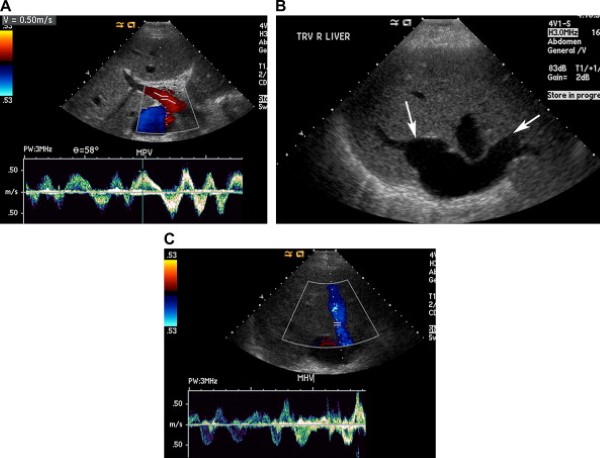

Hình ảnh siêu âm của hội chứng Budd-Chiari

Nên nghĩ tới hội chứng Budd-Chiari khi siêu âm thang xám không nhìn thấy các tĩnh mạch gan. Các dấu hiệu thêm vào gồm có thành tĩnh mạch gan dày, khẩu kính các tĩnh mạch không đều, và tĩnh mạch bàng hệ ngoằn ngoèo. Bệnh nhân hhường kèm theo gan to và tràn dịch ổ bụng. Phì đại chủ yếu ở thùy đuôi là đặc trưng và thường xảy ra do dẫn lưu tĩnh mạch của nó biệt lập đổ vào tĩnh mạch chủ dưới (bên dưới hội lưu tĩnh mạch gan).

Siêu âm Doppler phổ và màu chứng minh không có dòng chảy, dòng chảy giảm tốc độ, đảo ngược dòng chảy hoặc dòng chảy rối với tốc độ tăng cao trong các tĩnh mạch gan [23]. Khi có dòng chảy trong các tĩnh mạch gan và tĩnh chủ dưới, thì hình dạng sóng từ ba pha chuyển thành dạng phẳng giống như tĩnh mạch cửa –“tín hiệu Doppler giả tĩnh mạch cửa”, phản ánh bán tắc xuôi dòng [1,25]. Tuy nhiên kiểu sóng này không đặc hiệu, và có thể gặp trong các tình trạng bệnh lý gây tăng áp lực trong nhu gan, như thâm nhiễm mỡ, viêm gan cấp, và xơ gan [25].

Khoảng 50% các bệnh nhân Budd-Chiari phát hiện tĩnh mạch thùy đuôi to với đường kính trên 3 mm, và dấu hiệu này được coi là đặc trưng khi không có suy tim (Hình 21) [25]. Tĩnh mạch này giãn là do thùy đuôi là thùy duy nhất trong gan dẫn lưu trực tiếp vào tĩnh mạch chủ dưới, và nó còn làm cầu nối tắt nhận máu của các nhánh bàng hệ trong nhu mô gan còn lại nên dẫn tới phì đại thùy đuôi và tĩnh mạch thùy đuôi [25].

Hình 21. Hội chứng Budd-Chiari ở bệnh nhân nam 30 tuổi có tiền sử hemoglobin niệu kịch phát về đêm và xuất hiện sưng phồng ổ bụng. (Hình A) Siêu âm màu phát hiện hẹp tĩnh mạch gan giữa với aliasing mầu gân chỗ nối của nó với tĩnh mạch chủ dưới (mũi tên). (Hình B) Ảnh siêu âm màu và Doppler cho thấy tĩnh mạch gan giữa thông, nhưng tốc độ dòng chảy tăng cao. (Hình C) Ảnh siêu âm màu cho thấy tĩnh mạch thùy đuôi to (mũi tên) tĩnh mạch của nó dẫn lưu trực tiếp vào tĩnh mạch chủ dưới. Hình ảnh cộng hưởng từ và sinh thiết gan xác định hội chứng Budd-Chiari.